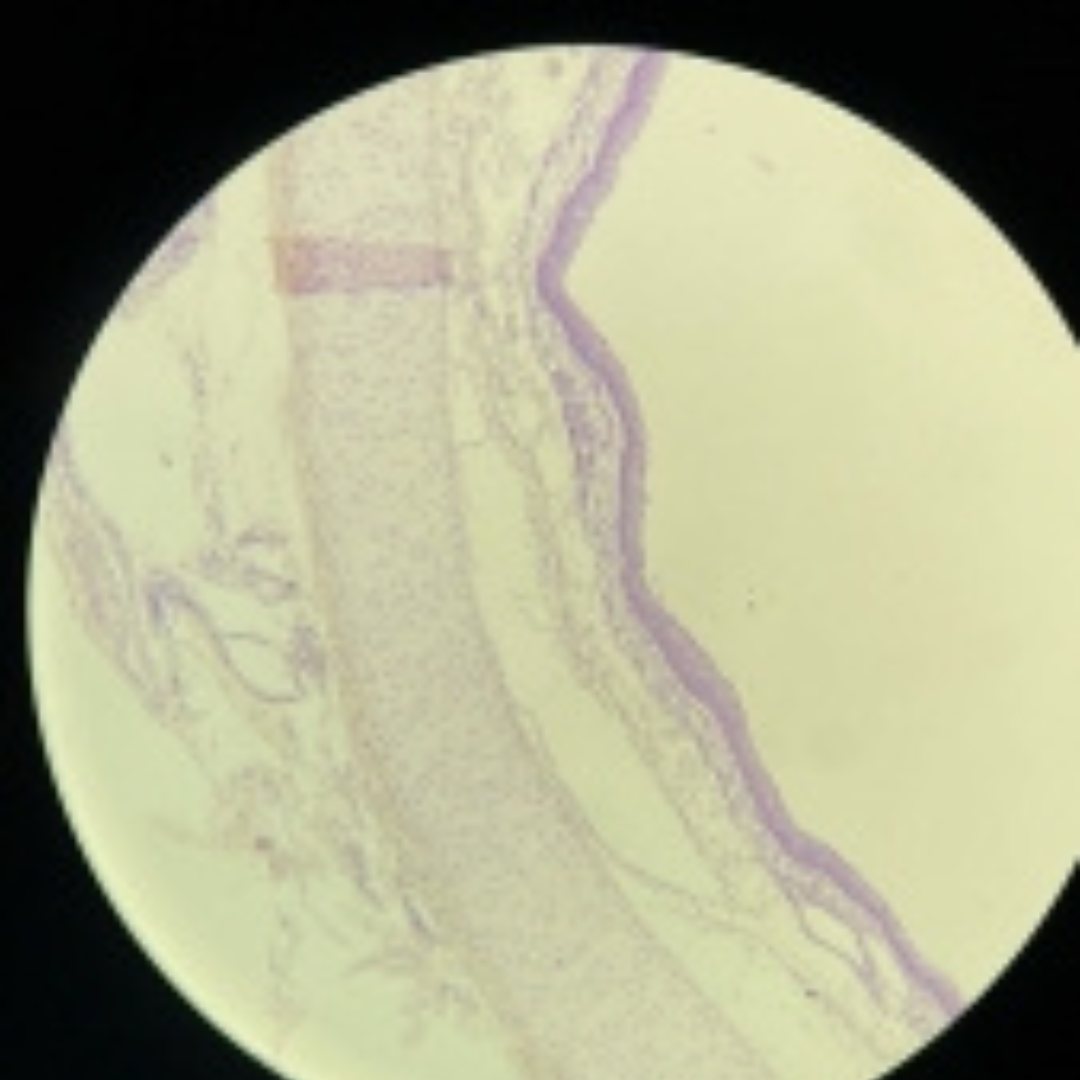

Large Veins

Large Veins

Large Veins

Large Veins